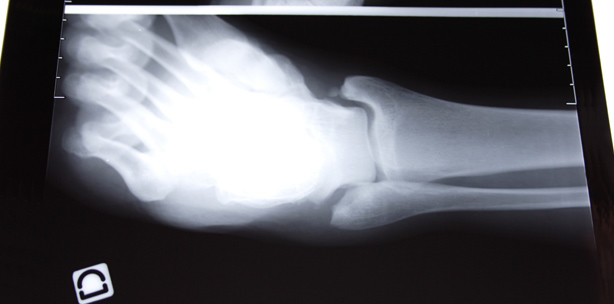

Seit Beginn des 20. Jahrhunderts kennt man eine Mangelerscheinung dieses Vitamins als Ursache für die Knochenkrankheit Rachitis. Vor allem Kinder, die im städtischen Lebensraum nicht genügend Sonnenlicht ausgesetzt waren, entwickelten diese Krankheit. Symptome sind z. B. deformierte Handgelenke, O-Beine und durch Vitamin D bedingten Kalziummangel verursachte Krämpfe. Heute wird Vitamin D als Ergänzungspräparat Kindern im ersten Lebensjahr verabreicht.